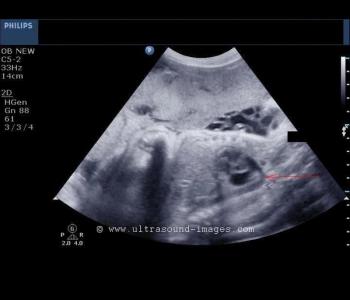

This middle-aged woman has a six-month history of menorrhagia, with no pain, resulting in anemia. What is your opinion based on these images?

This is a 2nd trimester pregnancy. What are your findings and diagnosis in this case (ultrasound images are of the pelvis and uterus in particular)?